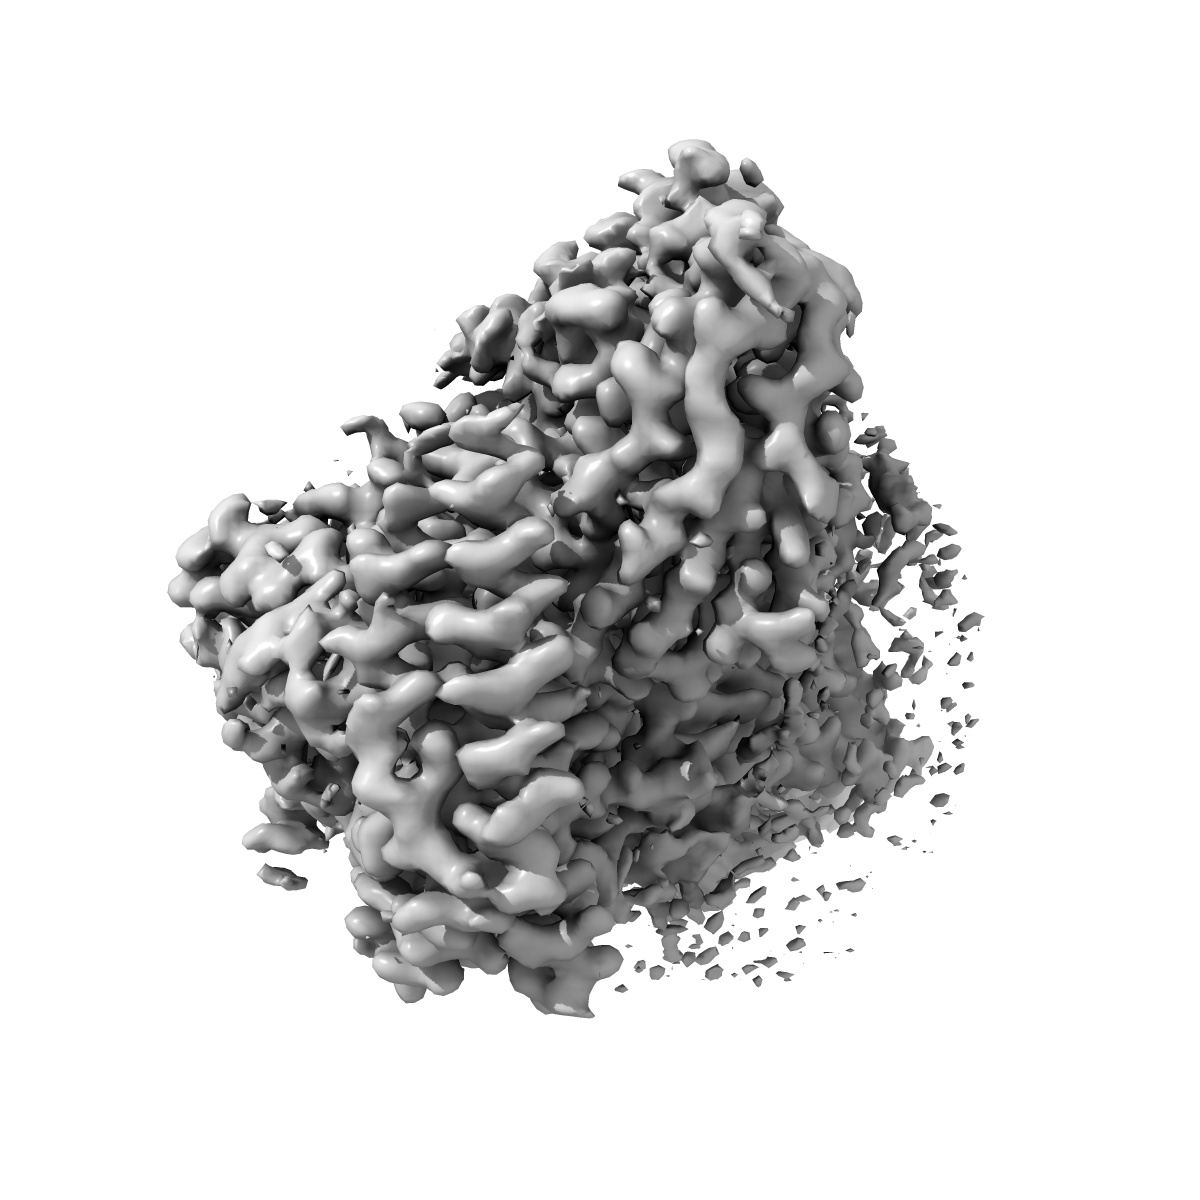

Cryo-EM structure of the PAC1R-PACAP27-Gs complex

Single-particle2.3 Å

Sample: Gs coupled Pituitary adenylate cyclase-activating polypeptide type I receptor complex with PACAP27 peptide